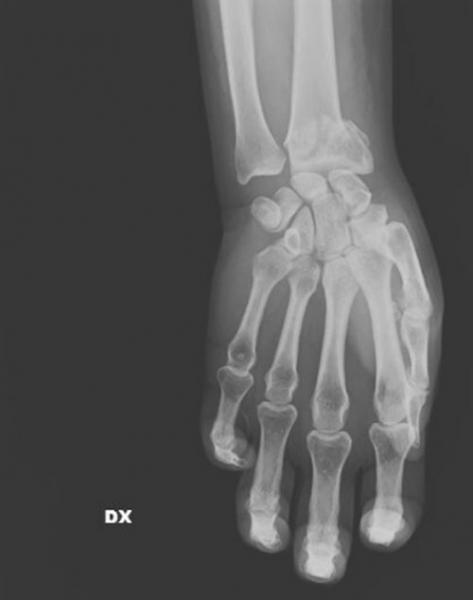

Σοκάρουν οι ακτινογραφίες από περιστατικά επιθέσεων κατά γυναικών - Εγκαύματα, μελανιές, σπασμένα οστά, σημάδια στραγγαλισμού, μαχαίρι στην πλάτη

Με αφορμή την Ημέρα, η ιταλική «La Repubblica» φιλοξένησε την γιατρό Μαρία Γκαρσία Βανταντόρι σε ένα εξαιρετικό αφιέρωμα το οποίο δημοσίευσε ακτινογραφίες γυναικών που έχουν πέσει θύματα ενδοοικογενιακής βίας.

Η Μαρία Γκράτσια Βανταντόρι είναι χειρουργός επί 26 χρόνια στο μιλανέζικο νοσοκομείο Σαν Κάρλο. Με πρωτοβουλία της πραγματοποιείται μια έκθεση ακτινογραφιών κακοποιημένων γυναικών.

Η ίδια αναφέρει πως στις ακτινογραφίες των θυμάτων αντικατοπτρίζεται η καθημερινή φρίκη που αντιμετωπίζει με τους συναδέλφους της στα «Επείγοντα».

«Συχνά οι τραυματισμένες γυναίκες δεν έχουν τη δύναμη να πουν τι τους έχει συμβεί, αλλά τα σώματά τους και τα τραύματά τους μιλούν από μόνα τους», σημειώνει, μιλώντας στην ισπανική εφημερίδα.

Σύμφωνα με την ίδια, καθημερινά καλούνται να αντιμετωπίσουν «σπασμένα οστά σε μύτη, χέρια, πόδια, πληγές από μαχαιριές, εγκαύματα, μελανιές και άλλα σημάδια στραγγαλισμού».

«Όλα αυτά τα χρόνια έχω δει χιλιάδες ακτινογραφίες γυναικών με κάθε είδους τραύματα, ακόμη και πολύ σοβαρά. Πολλές από αυτές τις κακοποιημένες γυναίκες αρνήθηκαν ότι τα τραύματά τους προκλήθηκαν από τους συζύγους ή άλλα μέλη της οικογένειάς τους. Η άρνησή τους σχετίζεται με συναισθήματα όπως φόβος, ντροπή, αγωνία για την τύχη των παιδιών τους ή και για τη ζωή τους ακόμη», σημειώνει η γιατρός.